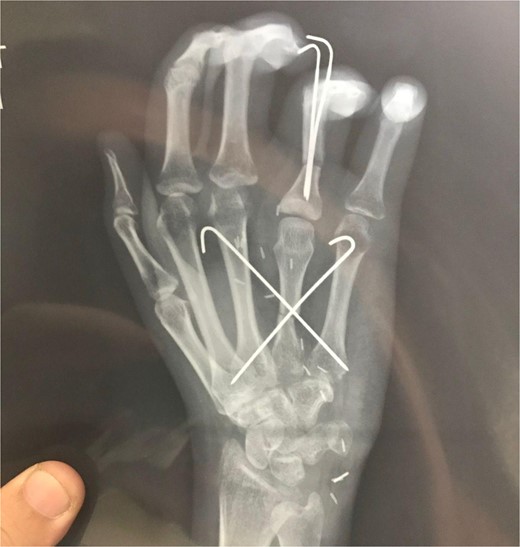

Post operatively the patient remained stable. The hand was kept in a dorsal back slab with bulky dressing with a hole cut out on the dressing for flap monitoring via handheld Doppler. Flap was monitored regularly over the arterial and venous anastomosis, already marked per operatively and doppler signals remained normal. Patient was discharged on the 4th postoperative day. Donor site wound showed good healing progress and no complications were noted. Postoperative X-rays showed satisfactory healing at both bony unions (Fig. 6). Regular dressings were done, K-wires were removed at 6 weeks and the patient was referred for physiotherapy of the small joints of the hand to regain functions. The patient showed good movement at the MCPJ at the follow up visits. She was able to do house chores and write normally. On examination there was slight medial rotation of the ring finger which the patient compensated by using her thumb. There was also slight flexion deformity of the distal interphalangeal joint of the ring finger (Fig. 7). No evidence of local or distant metastasis was present.